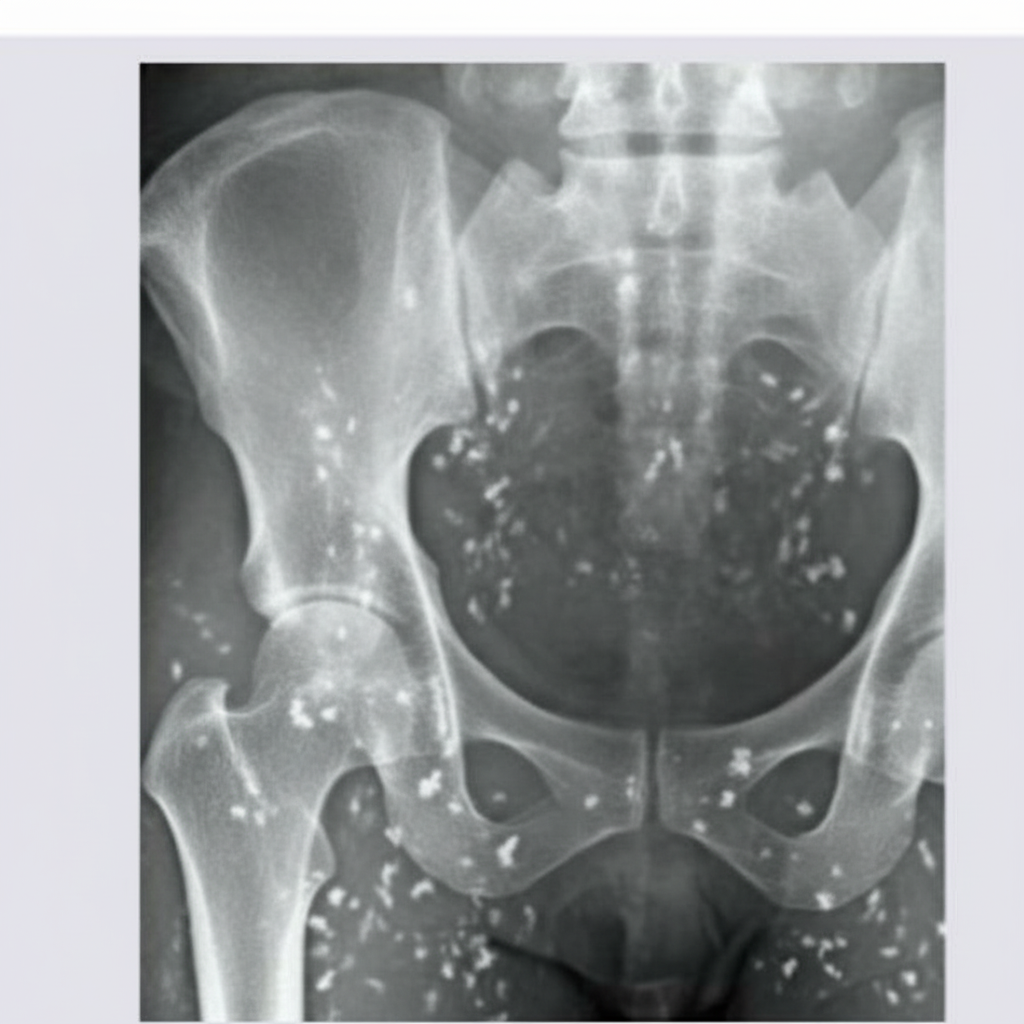

An expansile lytic lesion of the sacrum with specks of calcification is suggestive of which of the following?

Explanation: **Explanation:** **Chordoma** is a rare, slow-growing malignant tumor arising from the remnants of the **notochord**. It has a predilection for the ends of the spinal column, with the **sacrococcygeal region** being the most common site (50%), followed by the spheno-occipital (clivus) region (35%). Radiologically, it presents as a midline, **expansile lytic lesion** causing bone destruction. A key diagnostic feature is the presence of **internal calcifications** (seen in ~50-90% of cases), which represent residual bone fragments or intratumoral sequestration rather than true matrix mineralization. **Why other options are incorrect:** * **Osteosarcoma:** Typically occurs in the metaphysis of long bones (e.g., distal femur). While it shows bone destruction, it is characterized by "osteoid formation" (dense sclerosis) and aggressive periosteal reactions (Codman’s triangle), which are absent here. * **Secondaries (Metastases):** While common in the sacrum, they are usually multiple and rarely present as a solitary, midline expansile mass with specific calcification patterns unless from a primary like mucinous adenocarcinoma. * **Fibrous Histiocytoma:** This is a rare bone tumor that typically affects the ends of long bones. It presents as a lytic lesion but lacks the characteristic midline sacral location and calcification pattern of a chordoma. **High-Yield Pearls for NEET-PG:** * **Most common site:** Sacrococcygeal region. * **Histology:** Characterized by **Physaliphorous cells** (large cells with vacuolated, bubbly cytoplasm). * **Immunohistochemistry (IHC):** Positive for **Brachyury** (highly specific), S100, and Cytokeratin. * **Age group:** Typically occurs in the 5th to 6th decades of life.